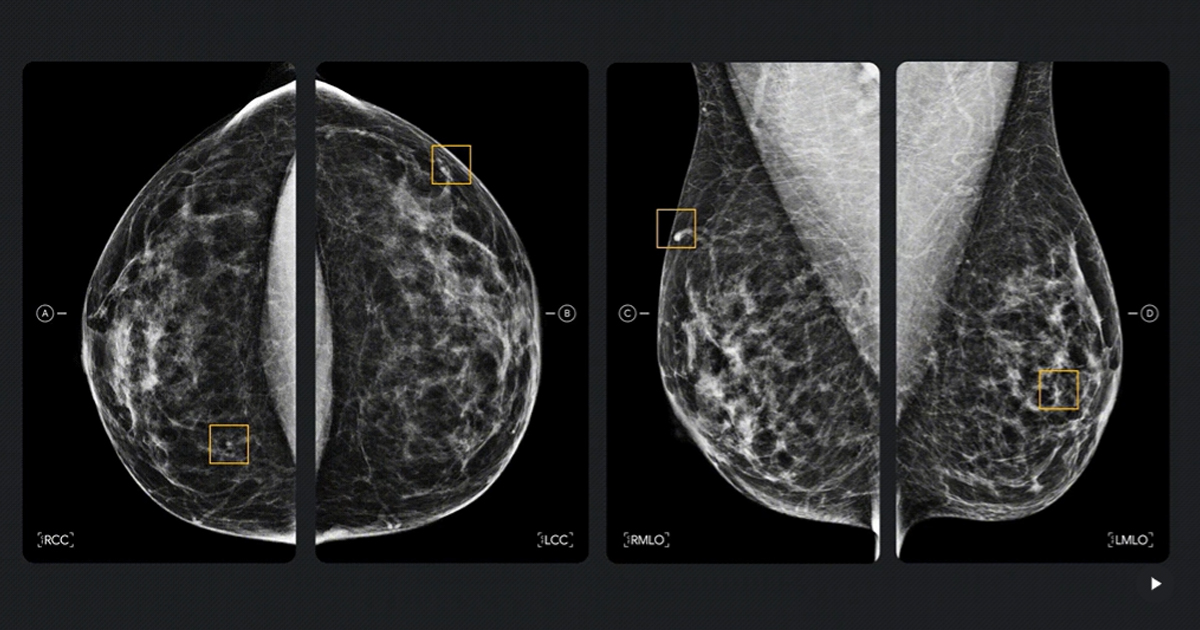

En materia de diagnóstico clínico, Google compartió los resultados de dos estudios realizados junto con el Imperial College London y el Servicio Nacional de Salud del Reino Unido (NHS, en inglés), publicados en Nature Cancer, que muestran cómo la AI puede mejorar la detección del cáncer de mama. El sistema de AI desarrollado identificó el 25% de los llamados “cánceres de intervalo”, casos que suelen evadir los tamizajes convencionales y se detectan solo cuando aparecen síntomas. En pruebas de integración con flujos de trabajo clínicos existentes, el sistema demostró potencial para reducir la carga de trabajo de los radiólogos sin comprometer la seguridad diagnóstica.